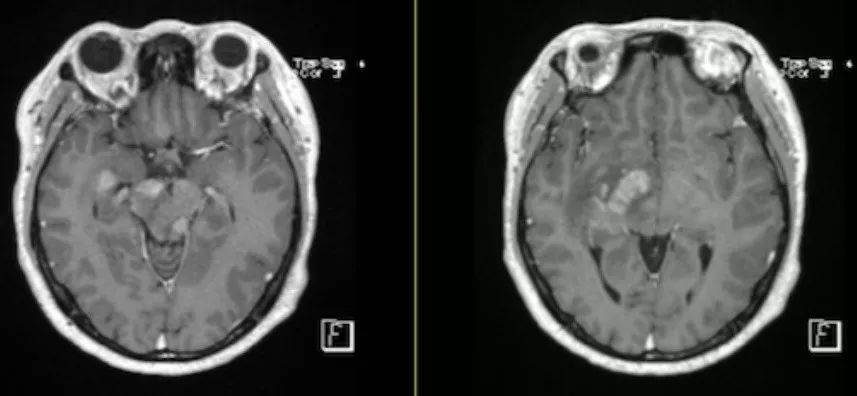

病例9(病例提供: 王浩玥 老师)

患者,女,55岁,因“突发视物重影1月,加重伴左侧眼睑下垂十余天”于入院,左侧上睑下,左眼向上、向下、向内活动受限,右眼各向眼动充分,伸舌右偏。

激素治疗半月后复查:

答案:间变性星形细胞瘤

好发于额叶、颞叶与顶叶的交界区,幕下少见。影像表现为浸润性肿块,主要累及白质。T1WI呈低信号,有出血时可见片状高信号区。T2WI呈高信号为主,常由于瘤内坏死而表现为混杂信号,DWI肿瘤实质部分呈稍高信号,坏死区呈低信号。瘤周水肿带呈长T1、长T2信号。通常不强化,少见局灶、结节样、均匀、斑片状强化。肿瘤组织可以通过细胞外间隙和沿白质束扩散,也可通过脑脊液和室管膜扩散,在播散通路上出现相似信号的肿块影。肿瘤内部不规整的线条状影指向周围脑实质,为本病较特征性的影像特点。